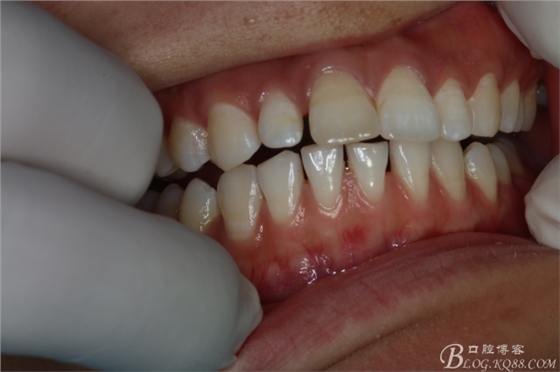

圖1.患者術(shù)前的口內(nèi)正面像:11和21前突、11和12有間隙